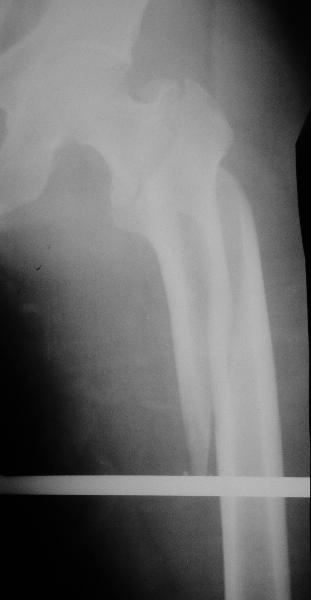

Дорогие коллеги,Как правильно определить такой перелом по классификации AO?

Как два отдельных или есть один соответствующий код? Фиксировать-то оба можно одним фиксатором...

AC >>Как правильно определить такой перелом по классификации AO? Как

AC >>два отдельных или есть один соответствующий код?

LAF>Мы пишем обе локализации по АО со знаком +...

AC >> Фиксировать-то оба можно одним фиксатором...

А что у вас где-то надо писать классификацию?

Какой метод выбрали для фиксации, имеется ли и другие рентгенологические проекции перелома?

Как раз недавно у меня был примерный случай: больному 36 лет, поступил ночью, травма в результате мотоциклетной аварии, кроме чрезвертельного и спирального перелома левого бедра имеется переломы костей предплечья с этой же стороны. Скелетное вытяжение, а на следующий день больной про оперирован на ортопедическом столе с дистракцией. Чтобы не расколоть чрезвертельный перелом провели временную спицу ближе к переднему кортексу, из малого разреза костодержатель для репозиции, а фиксацию провели антиградным штифтом. Этапы операции на снимках.